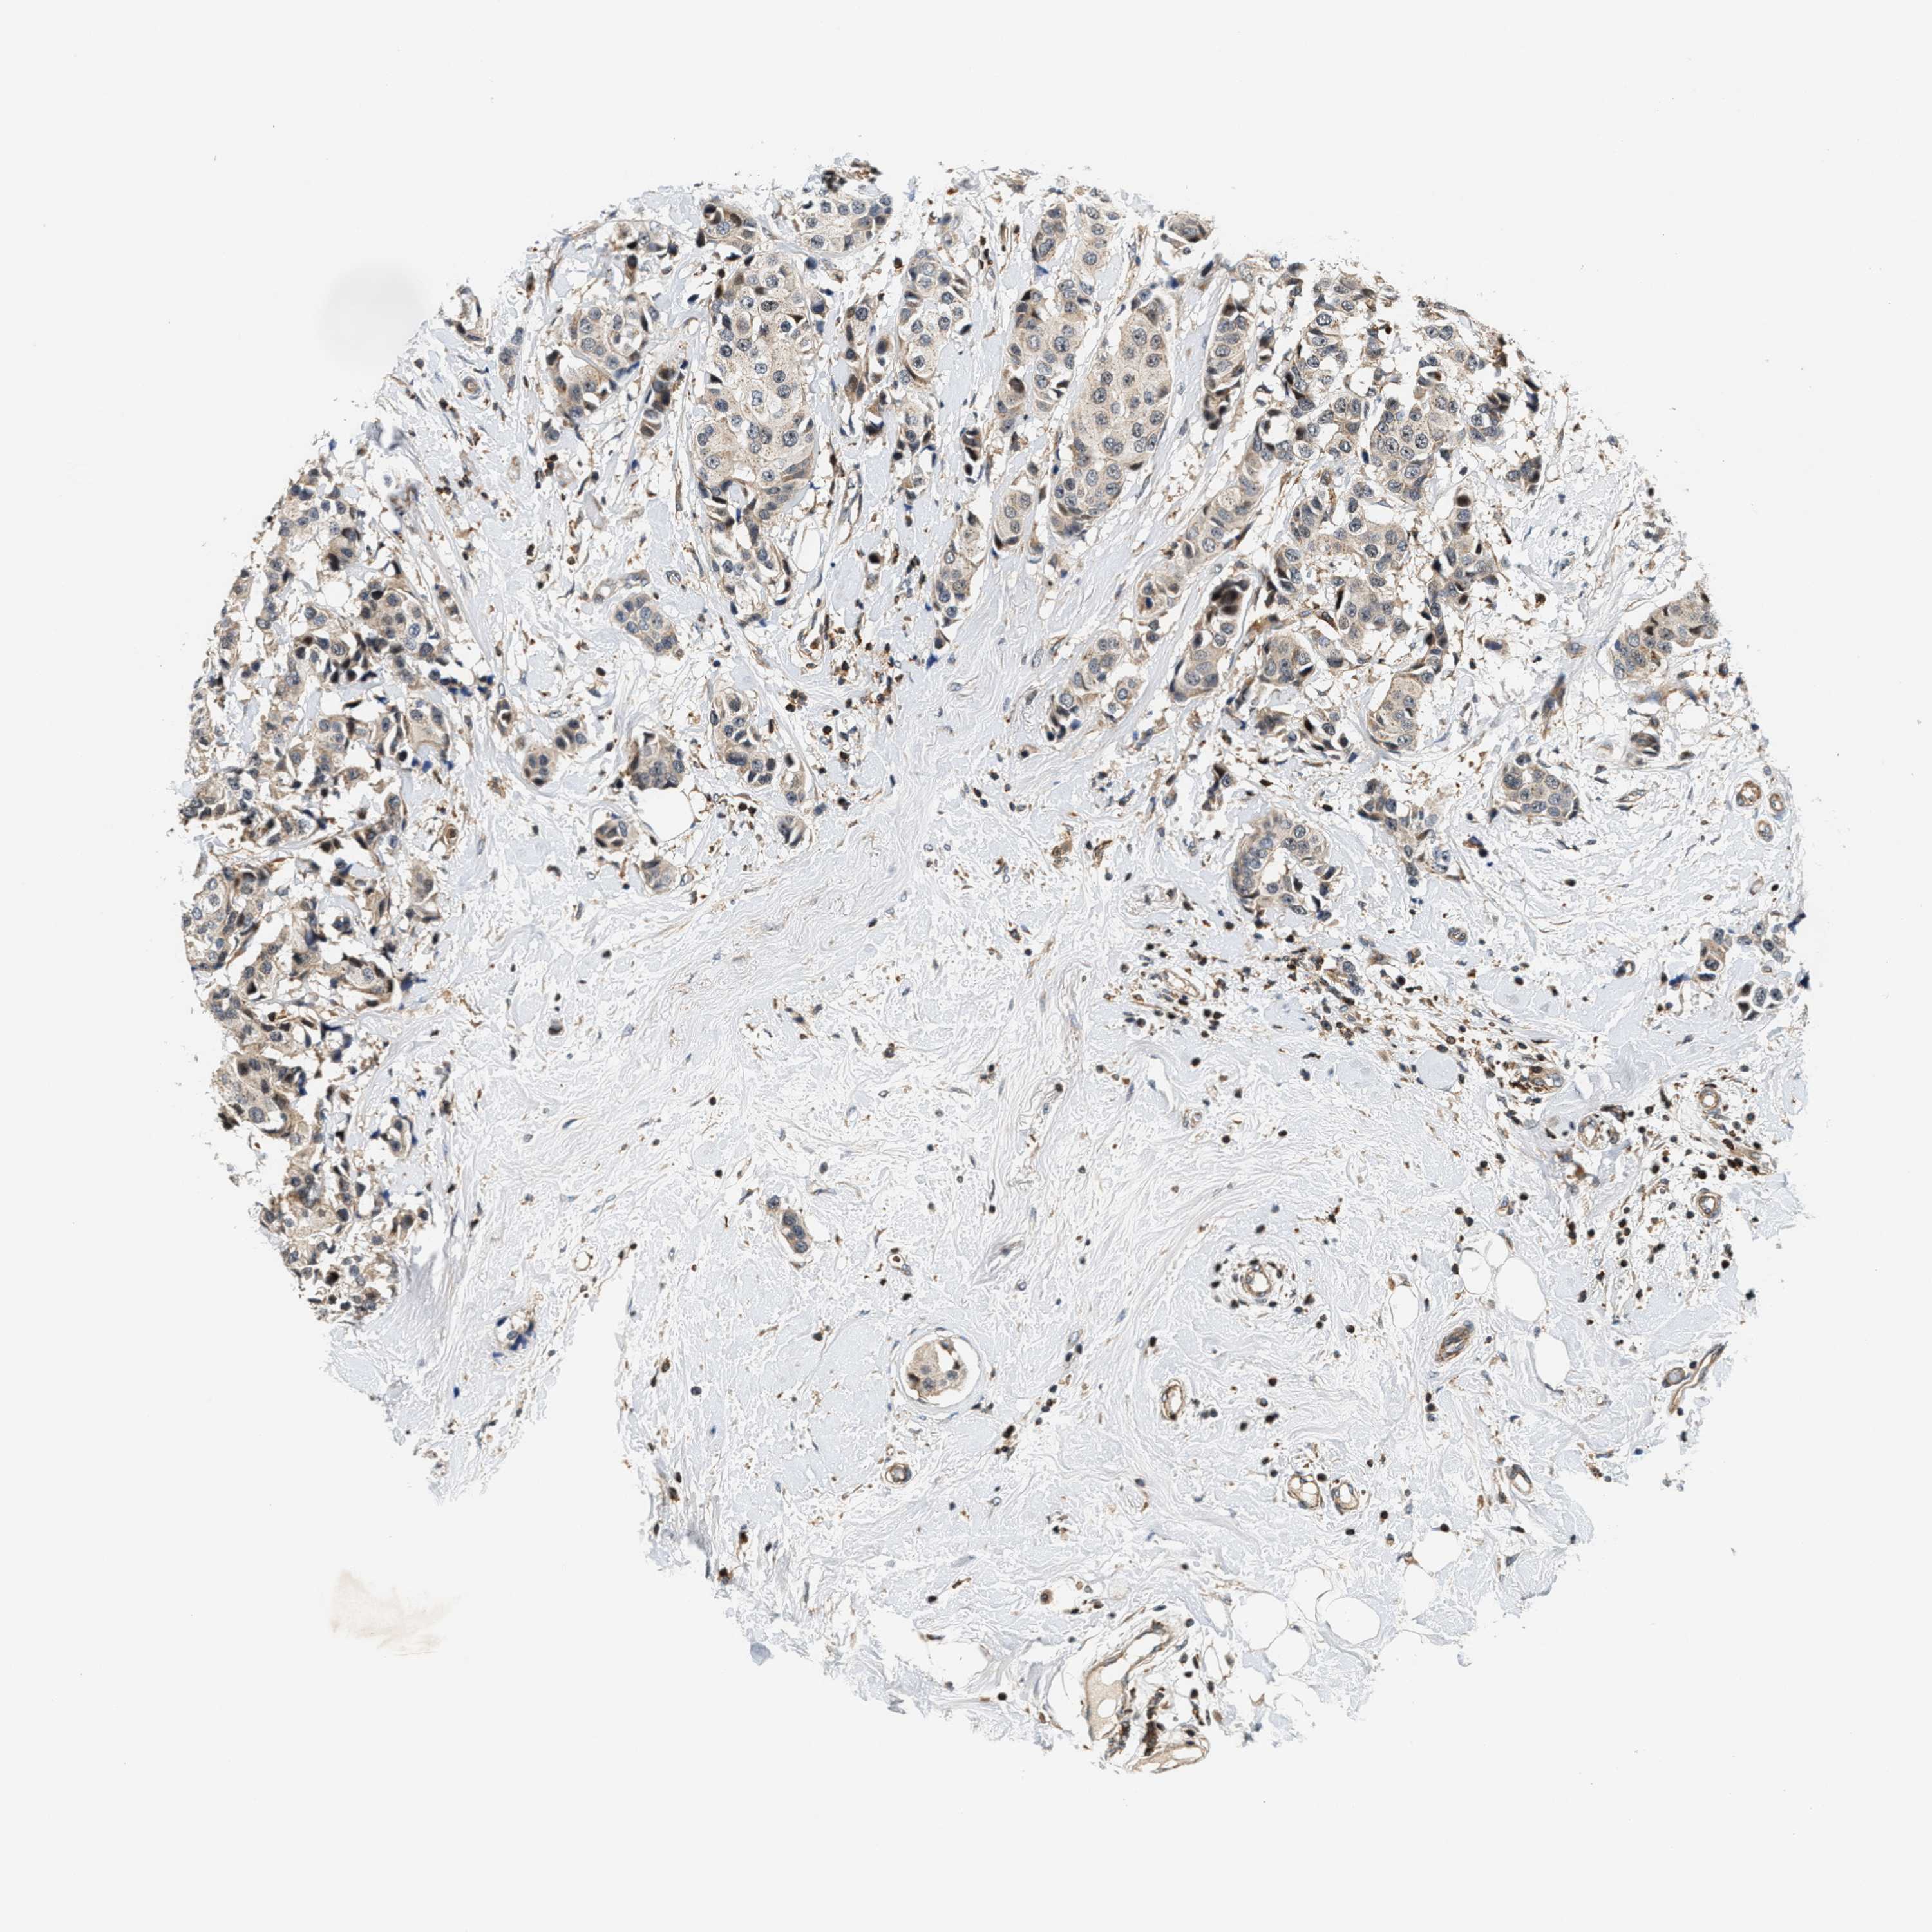

CANCER BREAST CANCER Show tissue menu

BRCA TCGA BRCA VALIDATION PROTEIN EXPRESSION